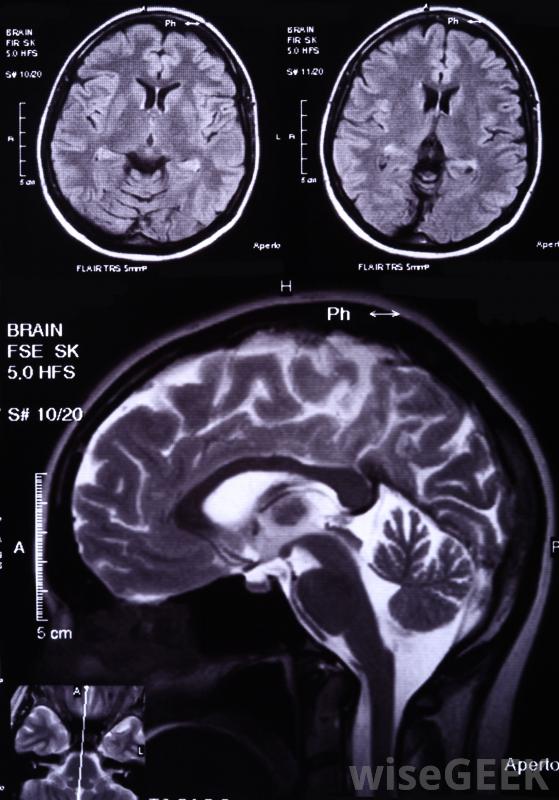

脑中最常见的肿瘤,胶质母细胞瘤,影响脑的支持细胞。复发性胶质母细胞瘤是由于肿瘤在治疗后发展而成,有时发生在远离原发灶的区域。这种肿瘤的大多数治疗方法试图控制肿瘤的复发,这种肿瘤可能发生在多个部位化疗包括将各种...

脑中最常见的肿瘤,胶质母细胞瘤,影响脑的支持细胞。复发性胶质母细胞瘤是由于肿瘤在治疗后发展而成,有时发生在远离原发灶的区域。这种肿瘤的大多数治疗方法试图控制肿瘤的复发,这种肿瘤可能发生在多个部位化疗包括将各种化学物质引入体内以杀死癌细胞复发性胶质母细胞瘤的治疗通常需要手术,只要有可能,医生通常会尽可能多地切除肿瘤,以防止肿瘤以后再次出现。有时,医生会选择放射外科手术,而不是侵入性手术,当聚焦射线直射肿瘤部位时,如果不同部位有多个肿瘤,放射外科手术通常是一种危害较小的选择,所需的治愈时间要少得多。